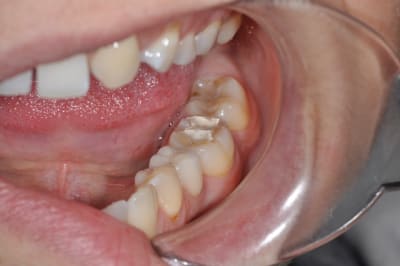

sur cette dent vous faites bio + inlay

ou alors, qui fait une CCC ?

37 semble aussi abrasée, donc je soupconne une abrasion et des parafonctions

couronne CAO

Si t'arrives à faire ton endo sans élargir plus la chambre, c'est une indication d'Inlay.

Mais il y a fort à parier au regard de la courbure importante de la racine mésiale qu'il faudra élargir cette chambre en mésiale, à ceci s'ajoute une carie débutante toujours en mésiale (sans parler des caries multiples un peu partout), donc on se dirige à mon avis vers de la prothèse périphérique.

Par contre le titre dit "bio et ensuite", ben ensuite, c'est soins conservateur multiples (y a du boulot), motivation hygiène (c'est bizarre toutes ces caries dans une bouche présentant un implant, signe de patient généralement motivé!), et enfin CCC.